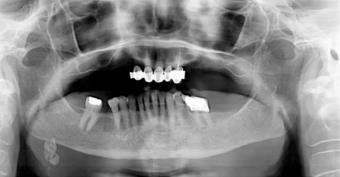

12.12. ábra. A jobb oldali gl. submandibularis hatalmas nyálköve

Patogenezis. A kristályok képződésének magjául sejttörmelék, idegentest vagy a nyál stagnálása következtében létrejövő szedimentum, ún. „nyákdugó” szolgálhat. A nyálkövek mérete igen változó, a gombostűfejnyitől a több cm átmérőjűig, színük a fehéressárgától a barnáig változhat. Organikus összetevők döntően kalcium-foszfátok és kalcium-karbonátok. Több nyomelemet is kimutattak nyálkövekből (pl. magnézium, réz, cink, mangán). A szerves és szervetlen anyagok sokszor egymással váltakozó rétegeket alkotnak, így a kő keresztmetszete lamellaris szerkezetet mutat, ritkábban hiányzik a mag, és a kő homogén szerkezetű (12.12. ábra).